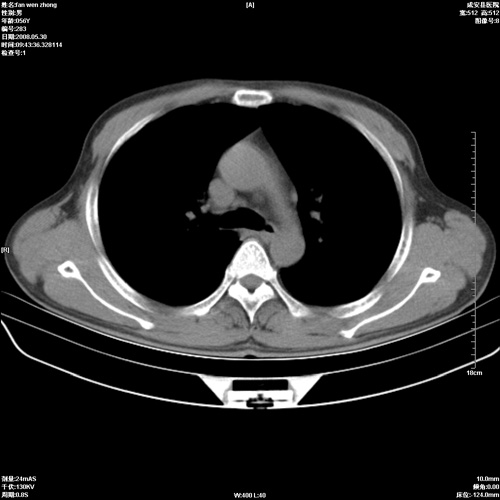

病人 男 56岁 一周前高热,体温达39-40度,经抗炎治疗后,体温渐降,达37,5-38度,轻微咳嗽,胸部不适 查白细胞为1.3万 行ct检查,请分析。

双肺内可见多发结节状病灶,并见小空洞,病人高热,白血球增高,应该是典型的迁徙性肺脓肿(多为金黄色葡萄球菌感染)。查一下口腔等其它部位有无感染灶。

双肺内可见多发结节状病灶,并见小空洞,病人高热,白血球增高,应该是典型的迁徙性肺脓肿(多为金黄色葡萄球菌感染)。建议治疗后复查.